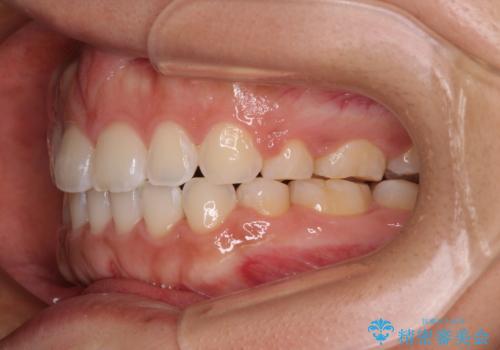

上下前歯部の被蓋関係を改善するの時間がかかり、3年間を要することとなりましたが、スッキリとした口元に仕上がりました。

気がつくと唇が開く 口元を下げる抜歯矯正